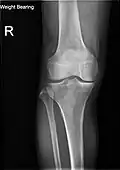

Radiography to examine possible fractures after a knee injury

Knee fractures are rare but do occur, especially as a result of a road accident. Knee fractures include a patella fracture, and a type of avulsion fracture called a Segond fracture. There is usually immediate pain and swelling, and a difficulty or inability to stand on the leg. The muscles go into spasm and even the slightest movements are painful. X-rays can easily confirm the injury and surgery will depend on the degree of displacement and type of fracture.